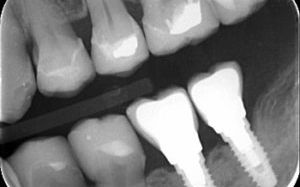

Multiple Teeth Missing

For a long time, removable partial dentures or fixed bridges were the only option to replace multiple missing teeth. Implants are the closest permanent tooth like treatment we have to replace multiple teeth.

If the adjacent teeth to the space are unrestored, healthy teeth, two implants can be placed next to one another to close the space. Alternatively, multiple implants can be used like a traditional bridge to replace more than two teeth.